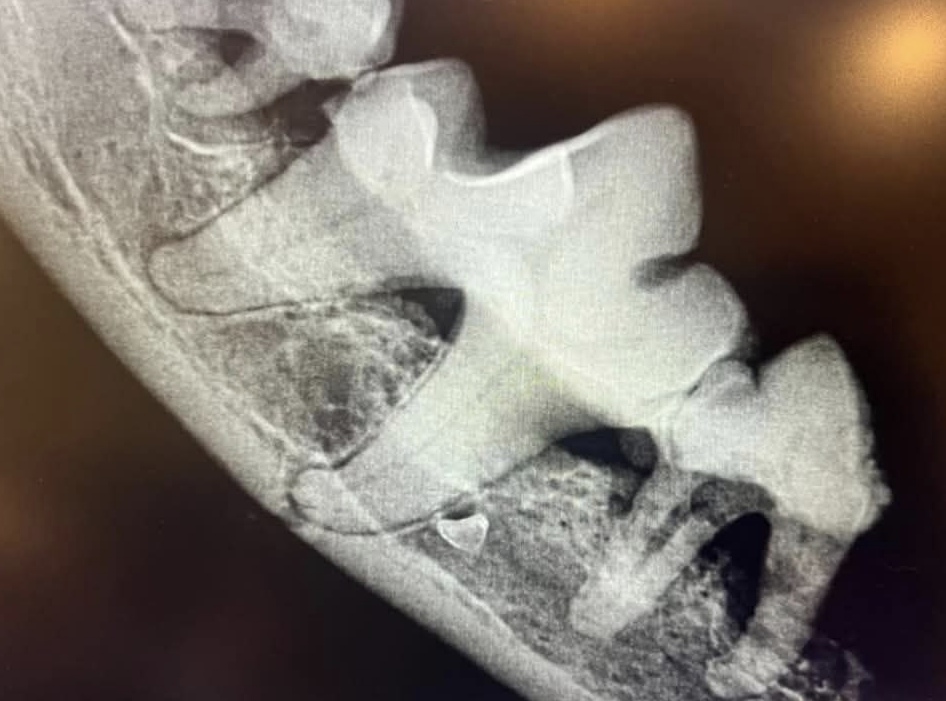

2. Рентгенография (дентальный рентген) — это один из самых информативных методов диагностики заболеваний ротовой полости у животных. С помощью рентгена можно выявить скрытые проблемы, такие как: — переломы корней зубов; абсцессы и воспаления в корневой зоне; резорбция зубов (часто встречается у кошек); непрорезавшиеся зубы или ретенции; состояние костной ткани челюсти. Дентальный рентген позволяет врачу увидеть то, что невозможно обнаружить при визуальном осмотре, и разработать оптимальный план лечения.